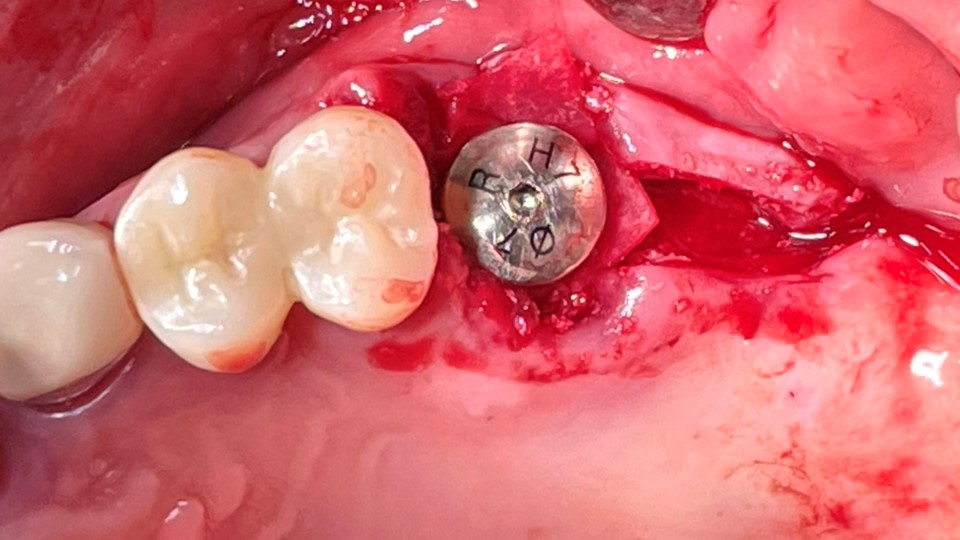

▲2 implants were placed. ArumDentistry NB1 5*10 (30Ncm) in the 1st molar and 5*10 (10Ncm) in the 2nd molar.

▲HA was inserted into the membrane with a hole in the middle and then inserted into the place where the Direction Pin was pulled out